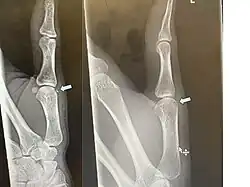

| Avulsion fracture of the proximal middle phalanx on the palm side | |